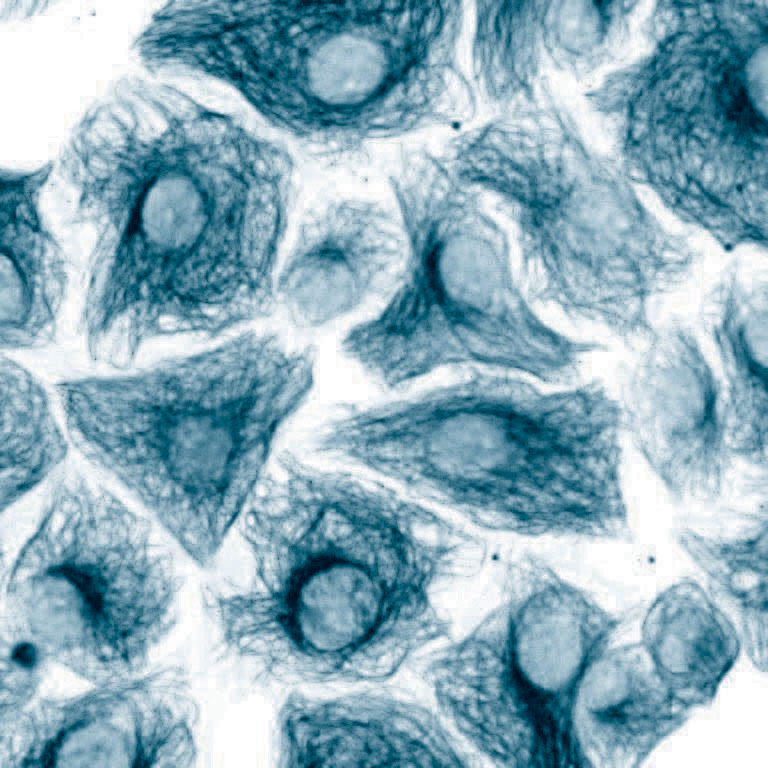

Opis:Na zdjęciu ukazano komórki T24 (nowotworu pęcherza moczowego człowieka) wraz ze strukturą cytoszkieletu, wybarwione znacznikiem fluorescencyjnym na czerwono. Fotografię wykonano za pomocą fluorescencyjnego mikroskopu konfokalnego ; Praca nadesłana na 3nd Microscopic Art Non-Limited International Annual Contest MANIAC 2021 ; kliknij tutaj, żeby przejść